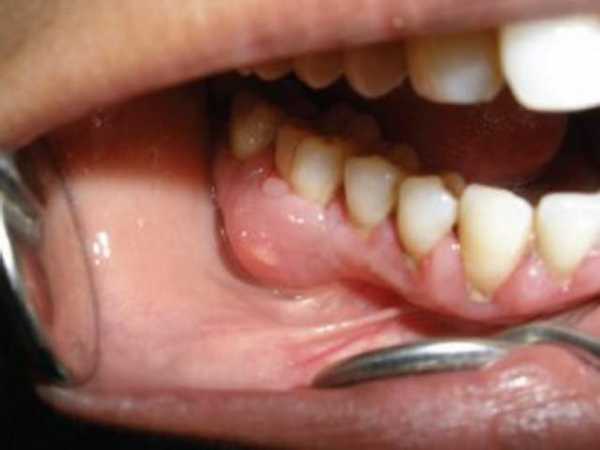

Простой флюс

- Простой флюс.Воспалительный процесс, протекающий в острой форме с развитием утолщения и гиперемии слизистой ткани.Развитие данного вида происходит на фоне перелома, ушиба, а также воспалительных процессов происходящих в челюсти и мышечной ткани рта.Воспаление всегда сопутствуют болевые ощущения и опухоль воспаленного участка десны.Болевые ощущения, как и опухоль чаще всего спадают, но бывает, что приводят к фиброзным образованиям, отложениям соли и развитием остеофита (новообразование костной ткани).

- Гнойный флюс.Возникновение гнойного флюса происходит по причине заражением стафилококками и стрептококками, а также некоторыми разновидностями грамположительных/грамотрицательных палочек и гнилостных инфекций.Гнойный флюс зуба появляется как осложнение периодонтита, также воспаление может образовываться при сложном появлении зубов и нагноением ретикулярных кист.Также флюс на десне может развиться после некачественного лечения или удаления зубов.

Гнойный флюс.

- появляется отечность различных размеров;

- происходит покраснение слизистой оболочки рта;

- возникают свищи.